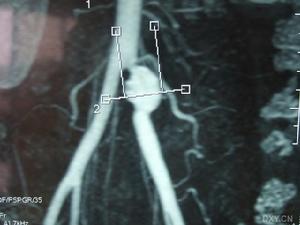

3.MRI檢查 無需造影劑便能顯示動脈瘤的大小、範圍、腔內血栓情況,清晰顯示動脈壁的各層結構,鑑別真性、假性動脈瘤。

4.動脈造影 是確定診斷和制定手術方案的最重要手段,可精確了解動脈瘤及周圍血管的情況,特別是流入道和流出道的通暢情況,對動脈瘤切除、血管重建術式的選擇具有指導意義此外,也有助於發現其他部位的動脈瘤。